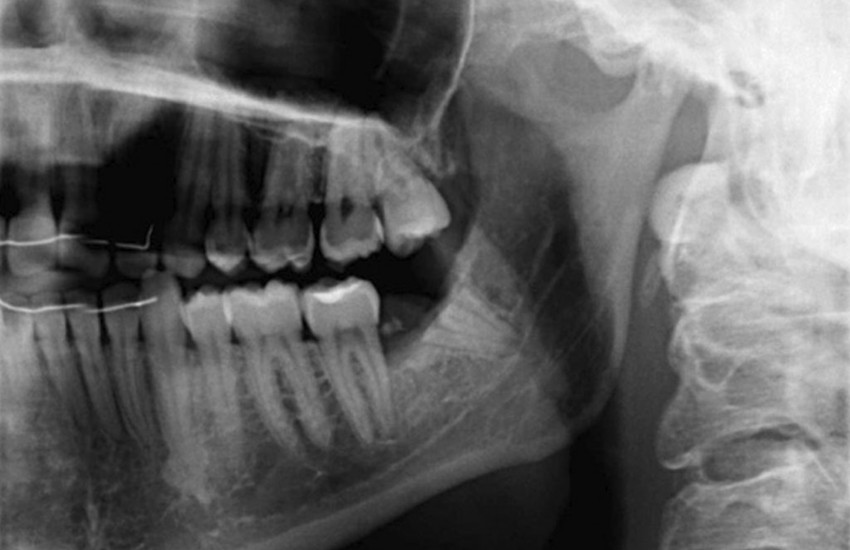

In certain cases, the roots of the lower wisdom teeth are positioned dangerously close to, or even wrapped around the inferior alveolar nerve, which provides sensation to the chin and lower lip. A standard extraction in this scenario poses a significant risk of nerve damage.

A coronectomy offers a safer surgical path by removing only the enamel portion (the crown) of the tooth that is causing decay or gum irritation. By leaving the healthy roots untouched within the jawbone, we eliminate the need to disrupt the sensitive nerve pathways nearby. Over time, the remaining root fragments typically become encased in bone or may even migrate slightly upward, away from the nerve, without causing further oral health issues.

At our Murphy, NC office, the decision to perform a coronectomy, which allows Dr. Bulsara to map the exact relationship between your tooth roots and the mandibular nerve. If a high-risk proximity is detected, we utilize precise surgical techniques to section and remove the crown while ensuring the remaining root structure is vital and free of infection.